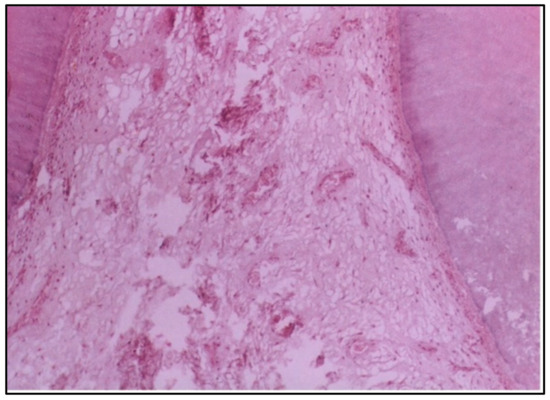

At 2 and 6 weeks, the specimens in the control group, which were not exposed to any restorative material, showed normal tissue architecture throughout the observation periods. The odontoblast cells were properly aligned, and the vascularity and cellularity of the pulp were normal. This confirms that the experimental changes in Groups I and II were due to the materials used and not due to natural tissue variation or a response to the experimental conditions (Figure 6).

The severe pulp response observed in one specimen with conventional composite resin was manifested by the presence of dense inflammatory cell accumulation and localized abscess formation beneath the cavity. This observation could be due to the presence of bacterial contamination during the filling procedure and/or microleakage and the long–standing bacteria and their endotoxins at the restoration/tooth interface. This finding has also been observed by Riberio et al. [20]. In contrast, the control group exhibited normal cellularity, vascularity, and odontoblast alignment at both 2 and 6 weeks. This highlights the natural regenerative capacity of the pulp tissue in the absence of irritants, reaffirming the importance of selecting biocompatible materials for restorative procedures [21].

Figure 6. LS of the pulp in situ (control group) showing normal cellularity, normal vascularity, and proper alignment of the odontoblast cells (H & E Stain, ×100).